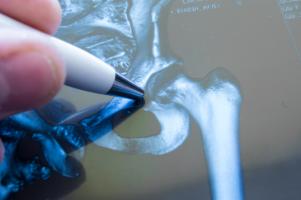

- ces hommes présentent en effet souvent des métastases osseuses, sources de douleurs osseuses et de fractures qui affectent également la survie ;

- les patients atteints de ce type de cancer métastatique sont généralement traités par thérapie de privation androgénique, une thérapie qui perturbe le renouvellement osseux et contribue au développement de maladies osseuses telles que l'ostéopénie et l'ostéoporose ;